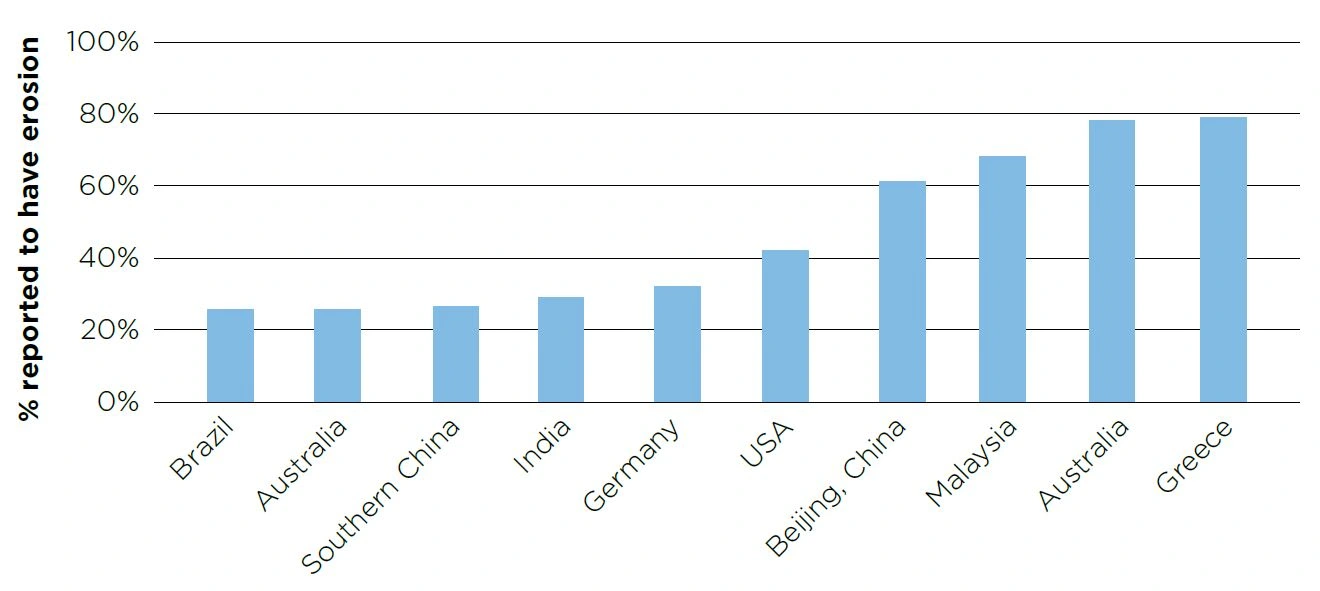

Dental erosion is prevalent in children and adults globally, with some researchers finding it present in approximately half of adolescents (Al-Dlaigan et al. 2001; McGuire et al. 2009). Estimated prevalence in some locations can be found in Figure 6.

Dental erosion is prevalent in children and adults globally, with some researchers finding it present in approximately half of adolescents (Al-Dlaigan et al. 2001; McGuire et al. 2009). Estimated prevalence in some locations can be found in Figure 6.